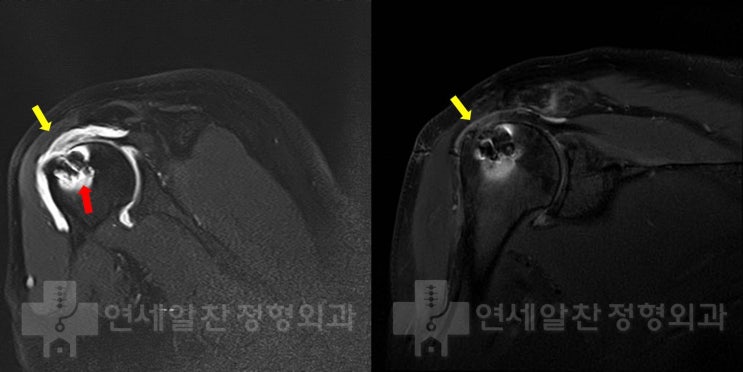

어깨 회전근개 파열 : 보다 단단하게 봉합하는 이열봉합법

안녕하세요. 정형외과 전문의 이동규 입니다. 오늘은 회전근개 파열에서 관절경 수술시 더 단단하게 봉합하...